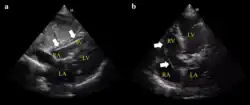

Ultrasound showing the device in the right ventricle

Ultrasound showing the device in the right ventricle The device inappropriately passing into the inferior vena cava

Example of ECG off the device a) free floating in the RV b) in contact with the RV wall It is possible to place the lead in the coronary sinus, normal (left) dilated (right). Such placement is okay.

It is possible to place the lead in the coronary sinus, normal (left) dilated (right). Such placement is okay.